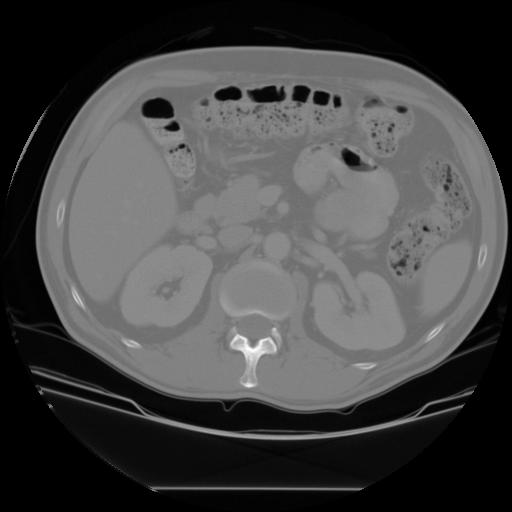

The main goal of this assignment is to find organs of interest in CT images, using techniques of binary vision in Matlab. The organs of interest are the kidneys, the liver, and the spleen, as shown below.